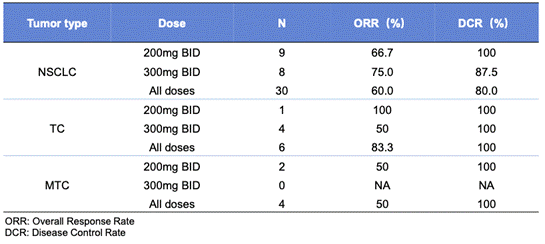

еЬ®40дЊЛеПѓиѓДдЉ∞зЪДжВ£иАЕдЄ≠�����пЉМзЛђзЂЛеЃ°жЯ•еІФеСШдЉЪеЗ≠жНЃRECIST v1.1з°ЃиЃ§зЪДжАїзЉУиІ£зОЗпЉИORRпЉЙеТМзЦЊзЧЕиКВйА†зОЗпЉИDCRпЉЙеИЂз¶їдЄЇ62.5%еТМ85%����гАВеЕґдЄ≠�����пЉМRETиЮНеРИNSCLCпЉИn=30пЉЙгАБTCжВ£иАЕпЉИn=6пЉЙгАБMTCжВ£иАЕпЉИn=4пЉЙзЪДORR/DCRеИЂз¶їдЄЇ60%/80%гАБ83.3%/100%еТМ50%/100����гАВиАМIRCеЬ® 200mgеТМ 300mgпЉИBIDпЉЙзЪДеЙВйЗПзїДдЄ≠жЙАжµЛеЃЪзЪДORRеТМDCRеИЂз¶їдЄЇ 66.7%/100% еТМ 75%/91.7%[1]����гАВ

и°®2.ORRгАБDCRдЇЖе±А